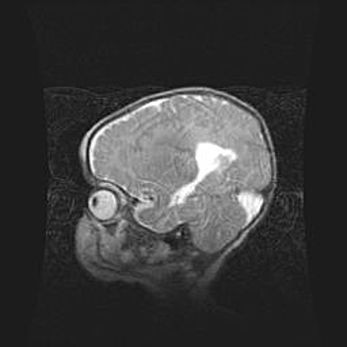

Аномалия Денди-Уокера. Признаки гипоплазии мозолистого тела.

Возраст: 5 месяцев 3 дня

Вес: 5550 г

Пол: мужской

Окружность головы: 39 см

Срок гестации: 40 недель

Аномалия Денди-Уокера – это порок развития головного мозга, для которого характерна триада симптомов: гипотрофия или аплазия червя мозжечка и/или полушарий мозжечка, расширение четвёртого желудочка с формированием ликворной кисты задней черепной ямки, гипертензионная гидроцефалия различной степени.

Гипоплазия мозолистого тела относится к дефектам внутриутробного этапа развития мозговой ткани, возникающим в процессе закладки структур головного мозга, что происходит на начальных этапах развития эмбриона.